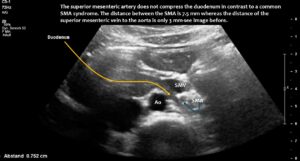

Normal size of the superior mesenteric vein which is slightly slimmer than the superior mesenteric artery as long as the patient was fasting. However, due to the limited space in the flat upper abdomen the superior mesenteric artery already is shifted to the left side of the aorta instead of lying precisely in front of it.

Here, the unique mechanism causing compression of the duodenum by the enlarged superior mesenteric vein is demonstrated. In contrast to conventional SMA syndrome, the superior mesenteric vein acts as a pillar against which the aorta presses, thus obstructing the duodenum. It is important to be aware of the variability in the position of the superior mesenteric artery in patients with a flat abdominal cavity. When the stomach is full, it may shift further to the left (or right) of the SMA than in the fasting position.